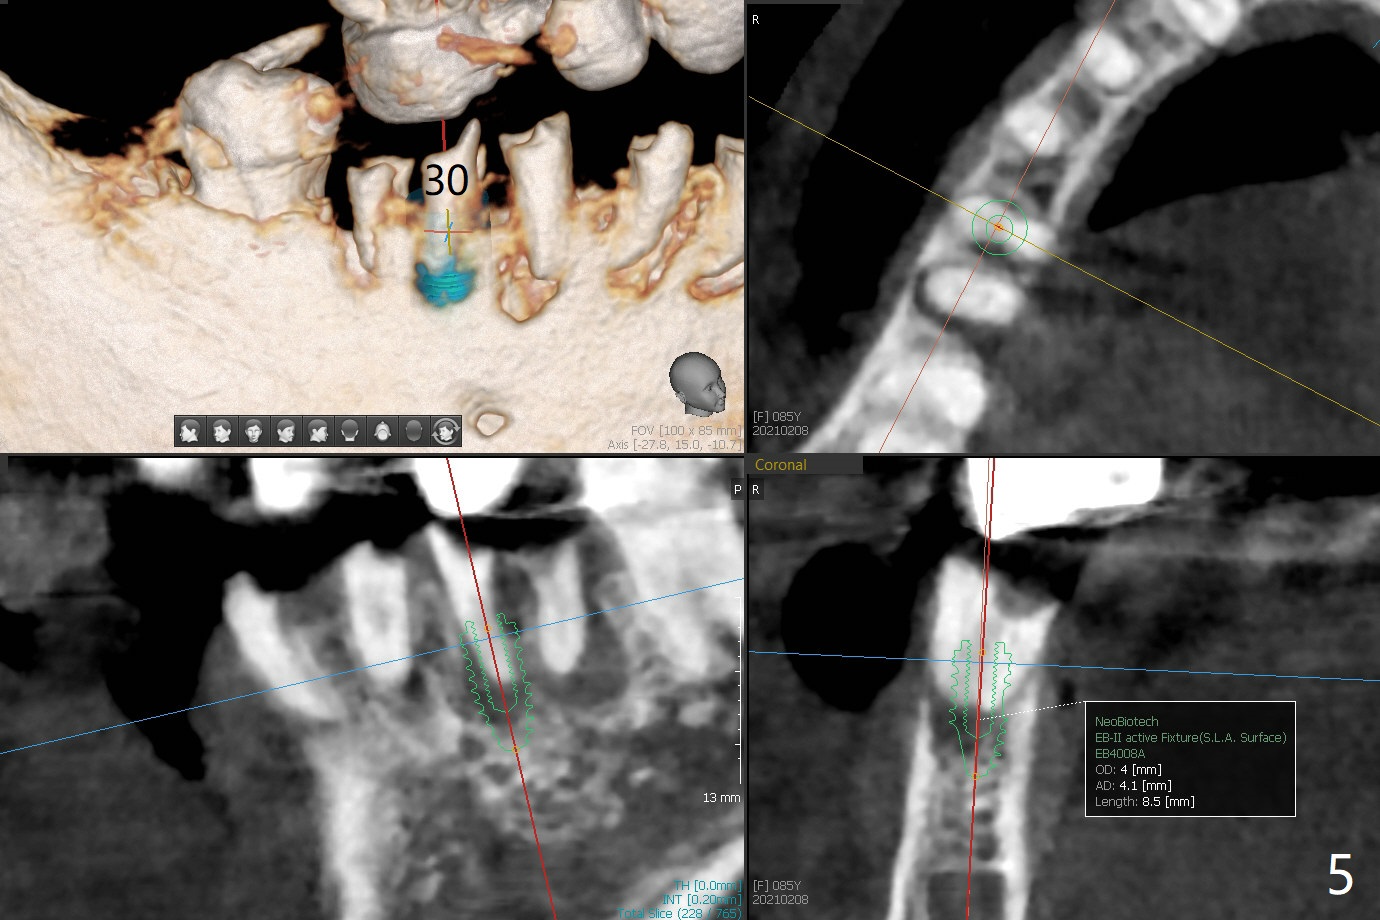

85岁女回诊所做27,28,30植牙,由于导板设计,所有7个残根需要拔除(图一,三),做过根管治疗牙齿(图一:箭头),如19,21号牙,颊侧骨板吸收比没做过的轻(图二,四:箭头(根尖穿孔))。30号牙根尖吸收多,使用短小植体(图五),根尖骨质少,初步稳定性差,不能即刻修复(图六),是这次手术最大欠缺的部分。原来准备在30号牙位做临时牙冠,局部托牙卡环恢复作用,还好27,28植体(图八)稳定性好,连体临时牙冠帮助托牙固定。27,28植体不足之处是放置太深,基台与牙槽骨(图八:*)接触,可能造成骨质吸收。其实27号植体(3.5x9mm)植入后必须去除,与基台连接后,一起徒手植入,所以深度控制不好。术后一个月10天病人回来做20和22号牙种植(拔牙后一,两个月),由于角化龈窄,切开导板植入,好处容易判断22号牙植体深度,植深后,两个植体周围放置骨粉(图九,十),然后胎盘膜(两个8x8毫米),4-0 PGA缝线。